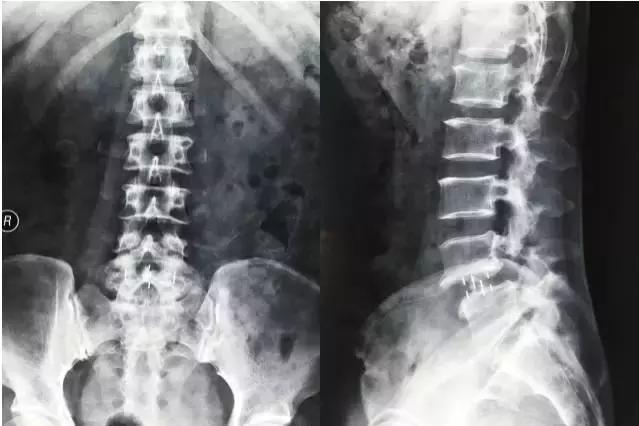

微创治疗真性腰椎滑脱症

▲手术前